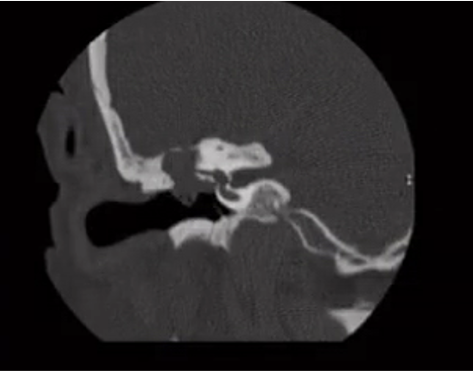

Classic EAC cholesteatoma. Axial bone algorithm shows soft tissue density within the medial left EAC with boney erosion and characteristic bone flakes.

Abnormal accumulation of keratin.